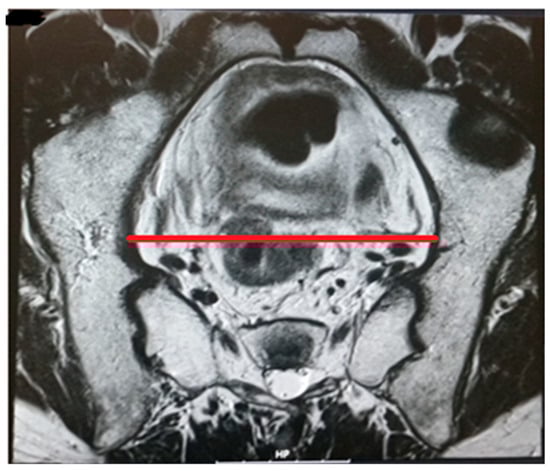

The pelvic measurements on MRI (Figure 2, Figure 3, Figure 4, Figure 5, Figure 6 and Figure 7) were carried out by the author, and to maintain the reproducibility of the results, measurements were taken, whenever possible, at the same anatomical levels.

Figure 3.

Transverse diameter.